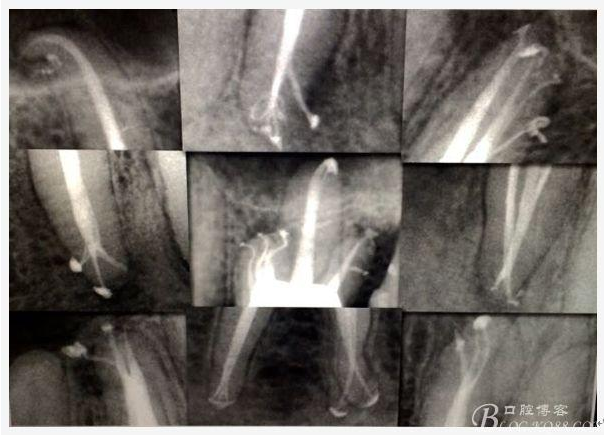

C、牙根的折裂與隱裂 包括橫折,縱折,或者斜折,外傷類的不用討論,主要是某些特殊原因比如牙齒本身結構先天性缺陷再配合后天因素如牙合創(chuàng)傷、咬合平衡發(fā)生改變導致應力集中,或者某次瞬間的咬合暴力等一種或者多種因素作用的結果,具體什么原因這個要從多方面因素權衡來判斷,比如牙齒的松動度,詢問病史,找不出其它原因時的重點懷疑,牙齒本事是否處于合應力集中的區(qū)域,是否有不良修復設計等等,具體可以通過臨床“理化檢查(冷熱,叩診等)”再結合數值化小牙片,牙髓活力測定,以及CBCT等來綜合判斷,重點懷疑牙為上頜的4/5的頰或者腭根,尤其是4或者5的遠中已是游離缺失或者單端橋等,6的腭根以及下頜的4/5/6都是重點懷疑對象,而最難診斷的是牙根的隱裂,即使使用CBCT有時候也沒辦法確診;

E 、X線影像學的檢查研判能力: 這點不需要強調太多,對于普通的非CBCT的二維影像對醫(yī)生讀片能力有一定的要求,有個逐步提高的過程,非一蹴而就,需要學會把二維的X線影像與三維的解剖結構進行良好的對應結合,對于某些鈣化的髓室底,應通過想象把根管口的分布、根管的走向以及各種變化通過想象投射到對應的髓室底上;